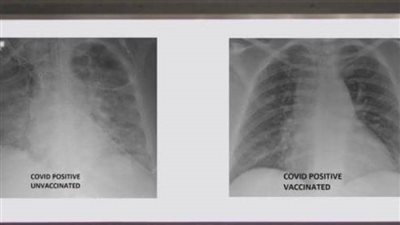

أظهرت صور الأشعة السينية، أن رئتي الشخص غير الملقح، المصاب بفيروس كورونا كانت بيضاء بصورة شبه كاملة وتعرف بـ"عتامة الرئة"، مما يعني أنها كانت غارقة في الفيروس